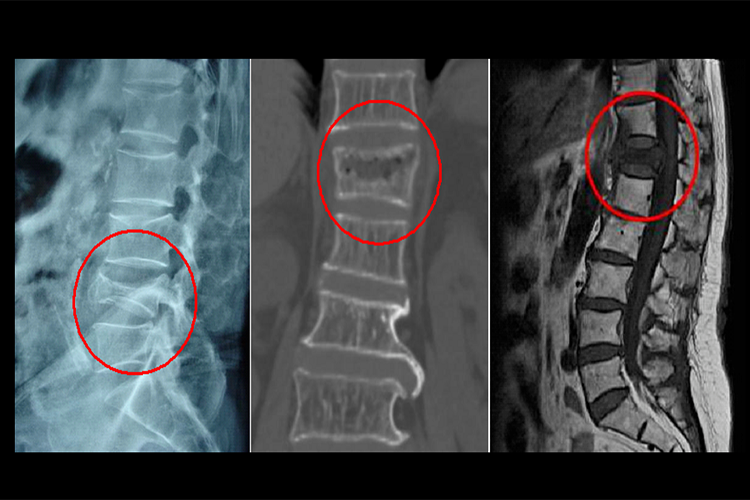

血行转移:肾细胞癌先侵犯肾静脉,导致静脉内形成癌栓,还可向远处转移到肺、肝、骨骼等处。